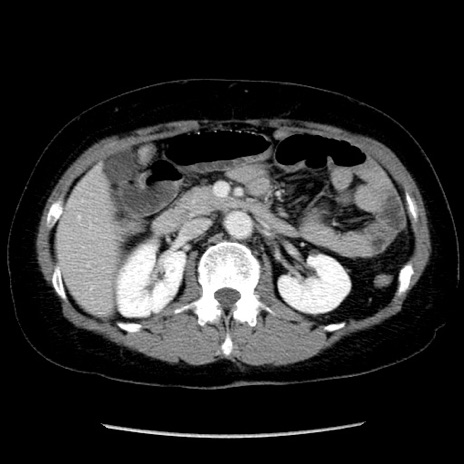

症例6(横断像)

【症例】50歳代女性

【主訴】下腹部痛

【現病歴】本日朝より下痢2回あり。 昼食を食べた後、嘔吐3回、下腹部痛認め、症状軽快せず、当院救急搬送。

最終食事:本日昼(生ものなし)。 昨日の夜、刺身を食ぺたとのこと。周囲に同様の症状の者なし。普段、排便は毎日あるとのこと。

【既往歴】卵巣癌術後(8年前に当院で卵巣摘出)

【身体所見】 意識清明、腹部:平坦、腸蠕動音→、やや硬、下腹部自発痛・圧痛あり、反跳痛あり、筋性防御なし。

【データ】WBC 16000、CRP 0.01